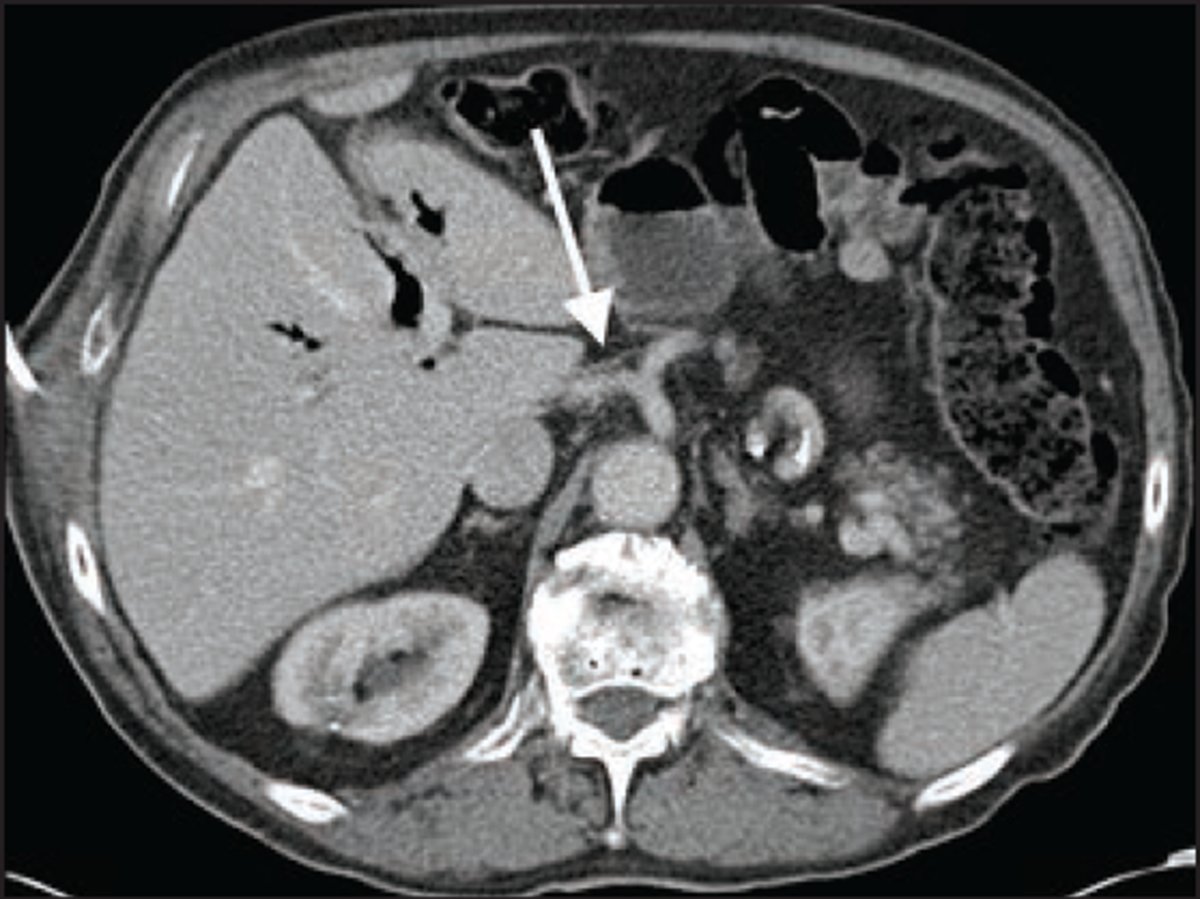

Co-author UCLA Radiology's Jena Depetris, MD & collaborators discuss "imaging strategies & important findings along the transplant timeline, from donor assessment to long-term recipient complications" in new Abdominal Radiology review. doi.org/10.1007/s00261…